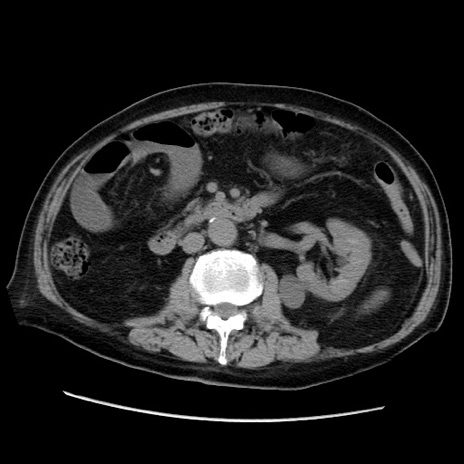

症例21(横断像)

【症例】70歳代男性

【主訴】腹痛

【現病歴】肝硬変・肝細胞癌にてかかりつけの方。約9時間前に食後より腹痛出現。症状が徐々に増悪し、嘔吐出現したため来院。

【既往歴】肝硬変、肝細胞癌(RFA、TACE後)

【身体所見】意識清明、表情苦悶様、BT 36℃、BP 129/78mmHg、P 88bpm、SpO2 97%(RA)、右上腹部から心窩部にかけて圧痛あり、反跳痛なし、筋性防御あり。

【データ】WBC 5800、CRP 0.16